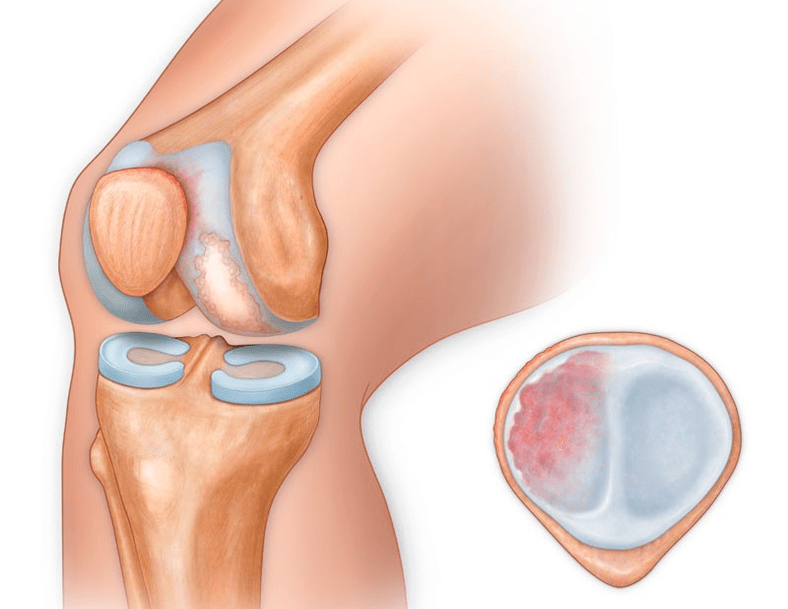

In addition to the internal or external part of the knee, osteoarthritis can also affect the surfaces between the patella and the intercondylar groove of the femur.This option is calledpatellofemoral osteoarthritis.

Its cause is usually subluxation, fracture or lateralization of the patella.